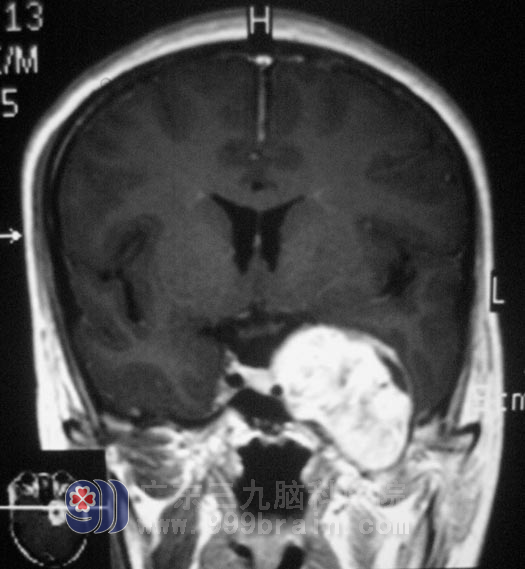

可是一个月过去后,症状没有缓解,昔日的笑容也有了变化。当地医院行头颅MRI检查,结果提示“左侧鞍旁占位”,家人拒绝开颅手术,认为风险高、创伤大,接受γ刀治疗。治疗后复查见肿瘤有轻微缩小,但是左侧颜面部麻木症状仍未有缓解。由于面部麻木有针刺感,她的笑容越来越少,同学们都称她是“冰美人”。

广东三九脑科医院综合神经外科 鲁明主任告诉她的家人:左眼颞侧视野缺损,结合病史,通过影像检查,考虑神经鞘瘤可能大:

8月16日由鲁明主任主刀,在全麻下行左侧中后颅窝占位切除术,术中见肿瘤呈灰白色,外上方有三叉神经粘连,后侧达脑干,血供丰富,质地较韧,与周围组织轻微粘连,在显微镜下予肿瘤分块,成功全切除。术后病理:(左侧鞍旁)神经鞘瘤。经过治疗,出院时的倩倩,笑容已恢复了往日的甜美。